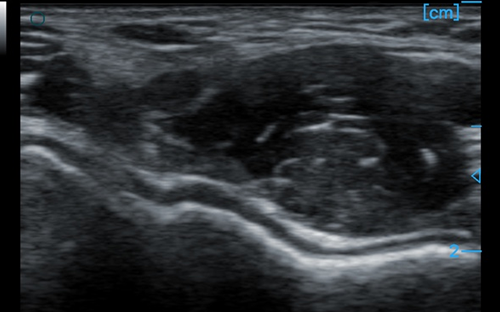

MSK

MSK